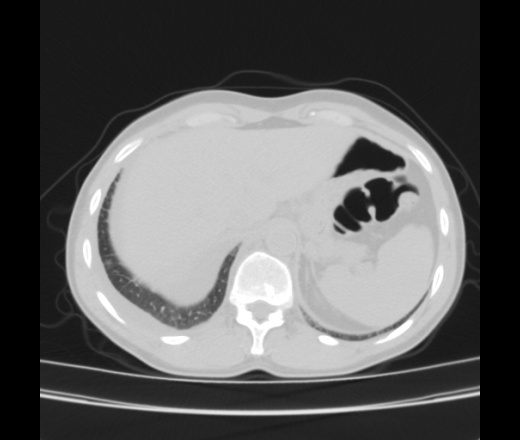

Женщина 55 лет. Жалобы на одышку, кушель с мокротой белого цвета, повышение температуры до 38, слабость, потливость, похудение. Больна в течение месяца. Лечилась в стационаре ЦРБ с пневмонией справа. Из выписки ОАК СОЭ-55, эр-лей-тромб - в норме. Мокрота на БК -. Анализ плевральной жидкости лейкоциты 12-13 , эритроциты измененые и неизмененые, клетки мезотелия.

За tbc c поражением внутригрудных л/узлов, правосторонним плевритом. Экс.перикардит. Признаки сердечной недостаточности.

Как второй вариант сочетание ЛГМ  и tbc, но тогда вопрос об имунном статусе.